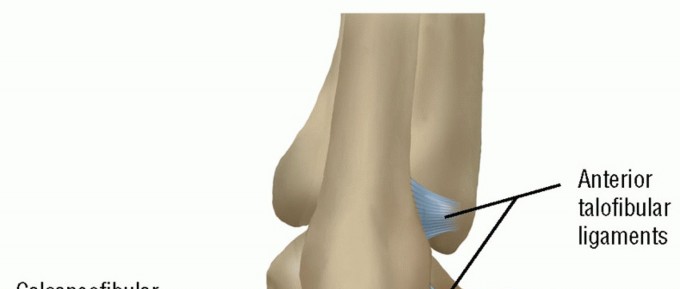

DEFINITION Lateral ligament instability occurs in some patients after an inversion injury. 38 Although an inv…

DEFINITION Lateral ligament injuries of the ankle are treated conservatively with good results in most cases.…